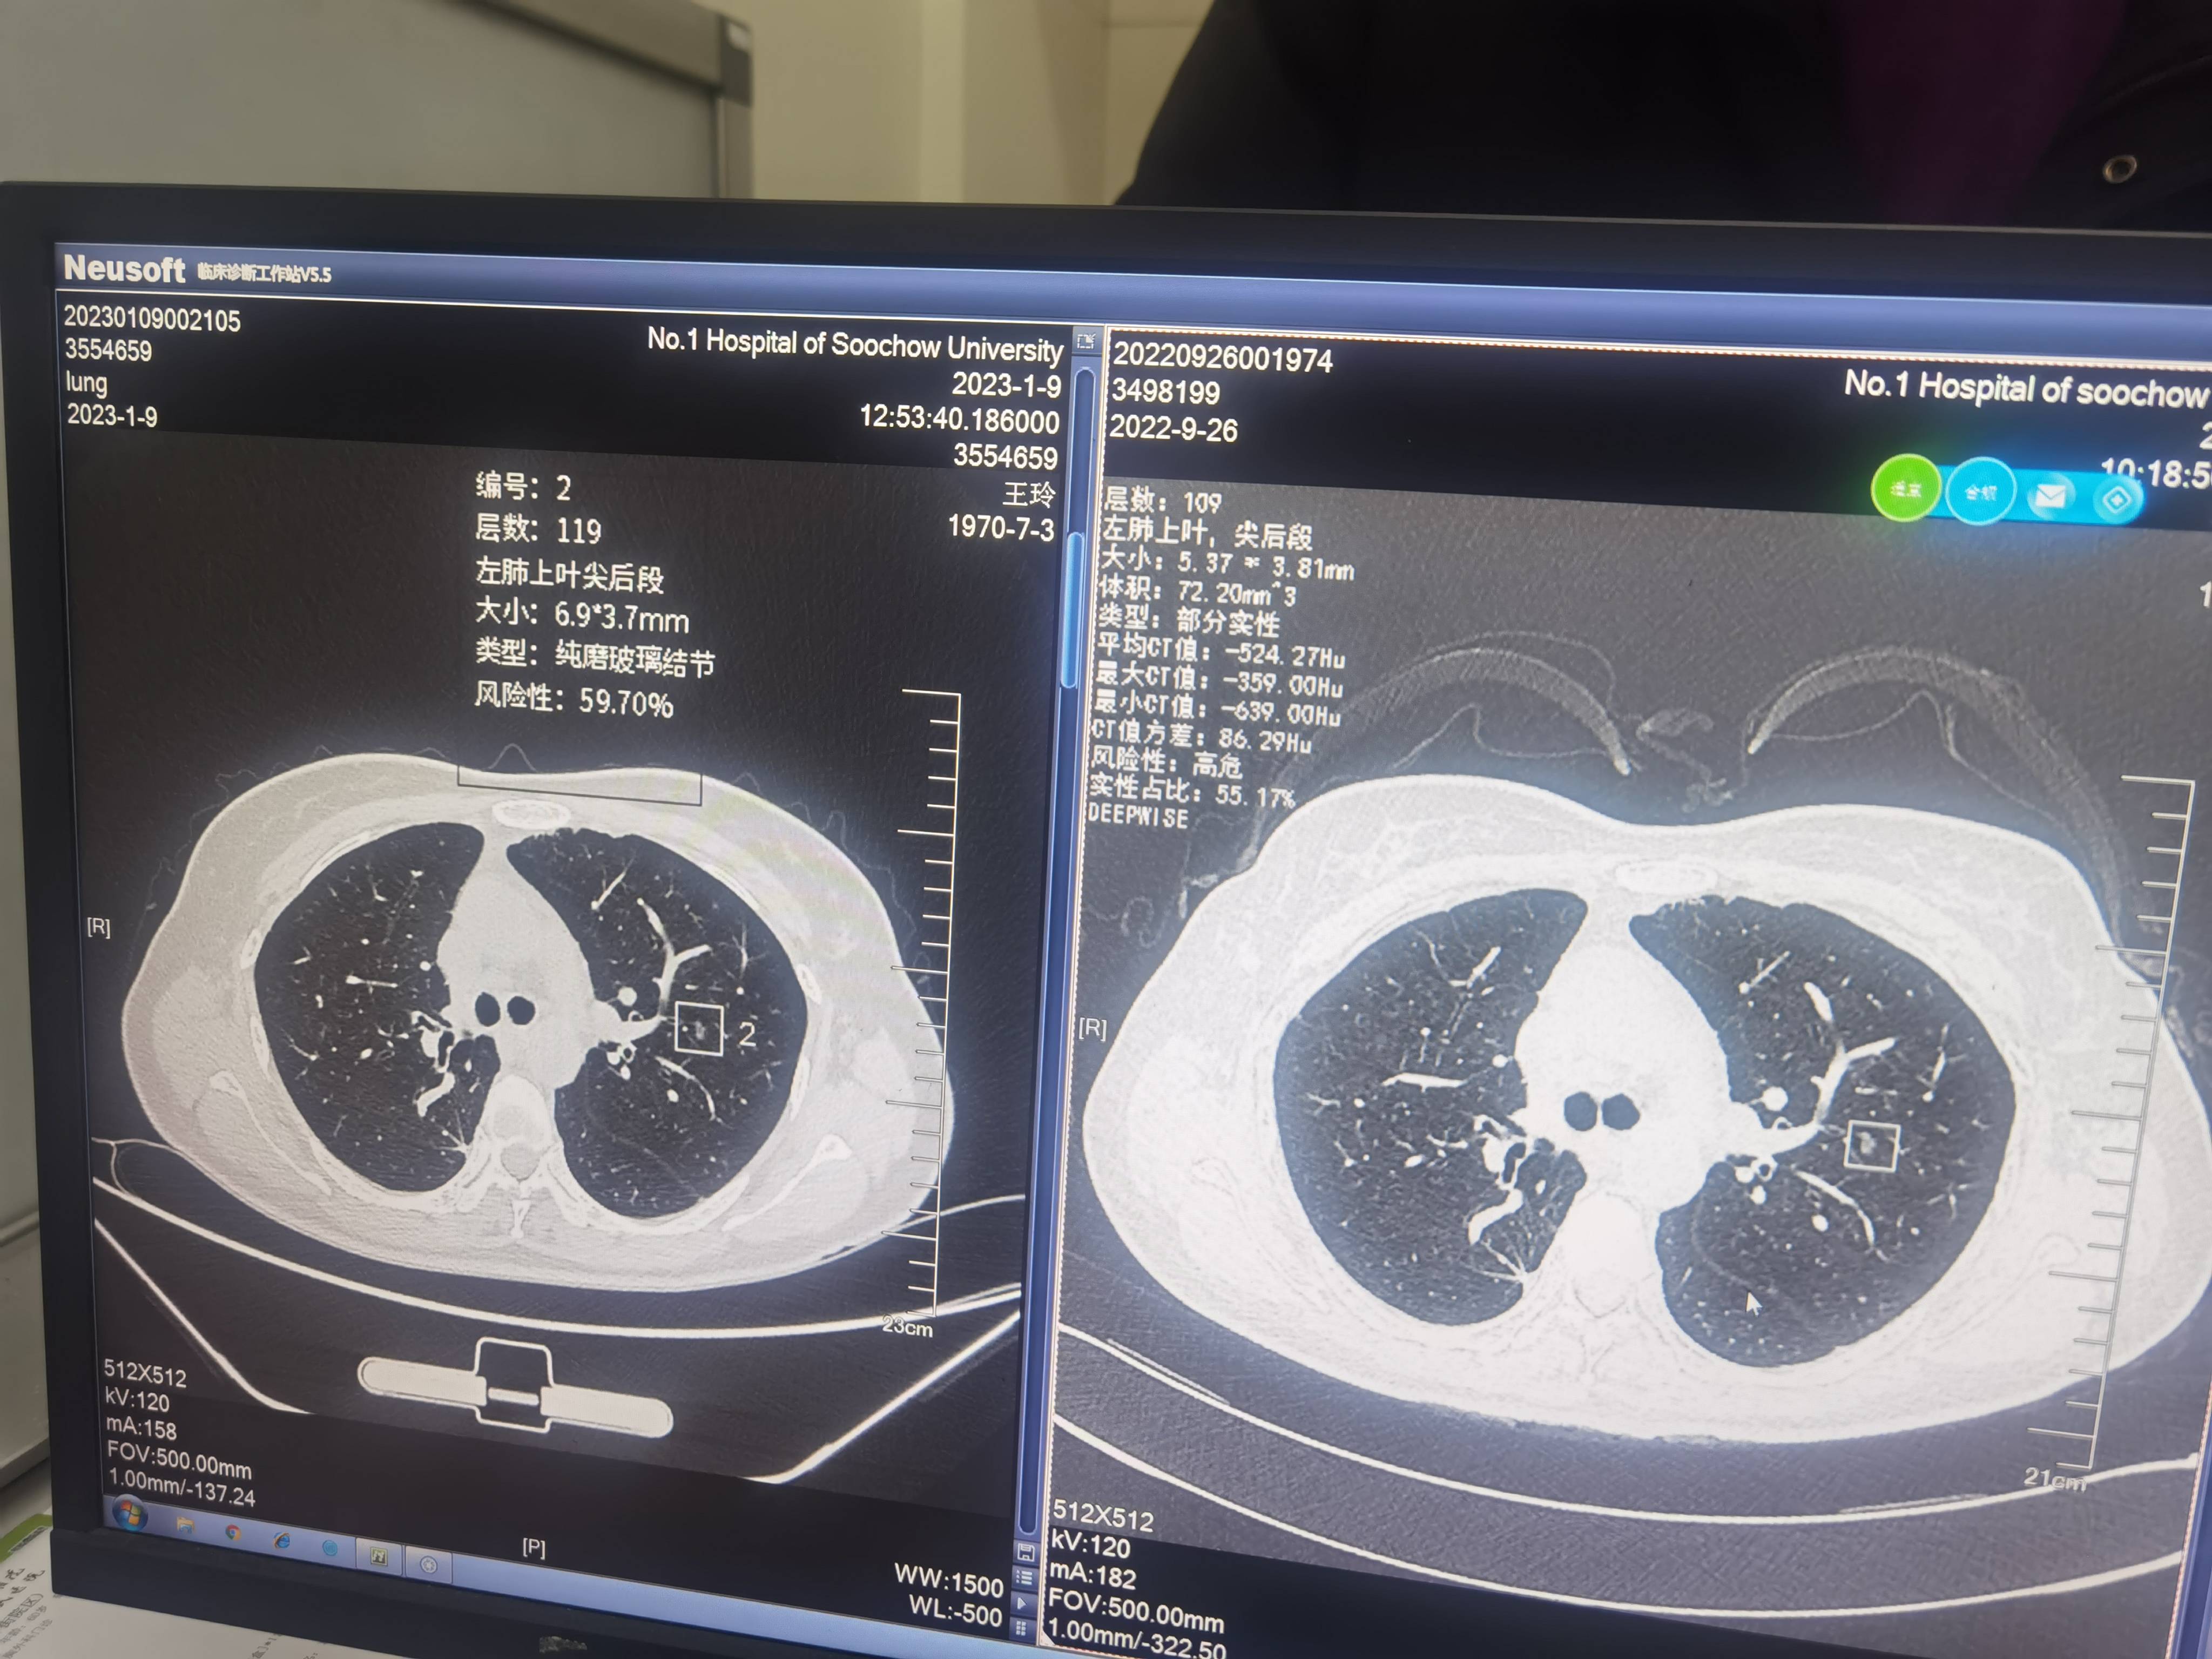

图片